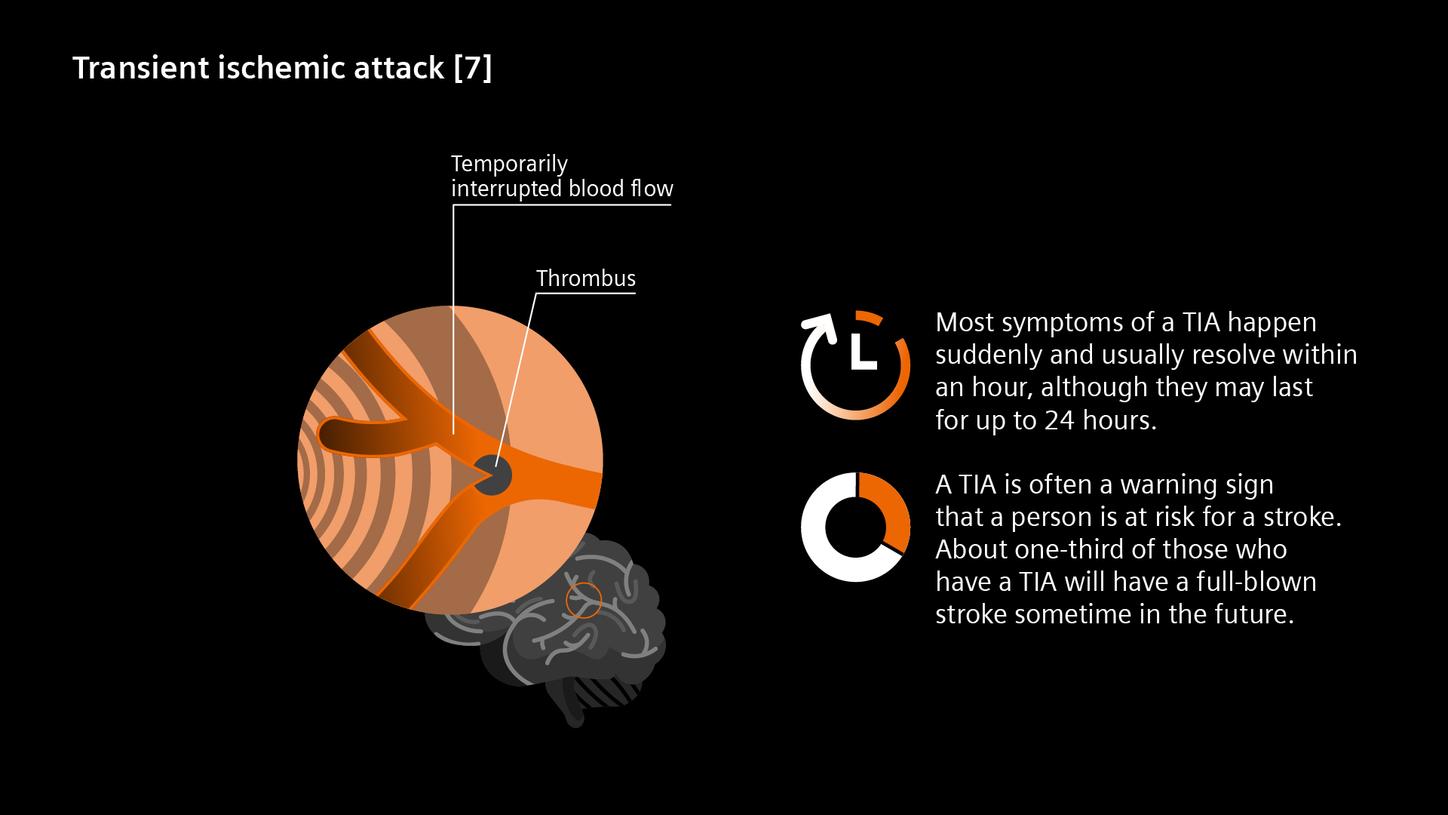

[7] Transient ischemic attack (TIA) [Internet]. National Institute of Neurological Disorders and Stroke. [cited 2025 Jun 12]. Available from: https://www.ninds.nih.gov/health-information/disorders/transient-ischemic-attack-tia